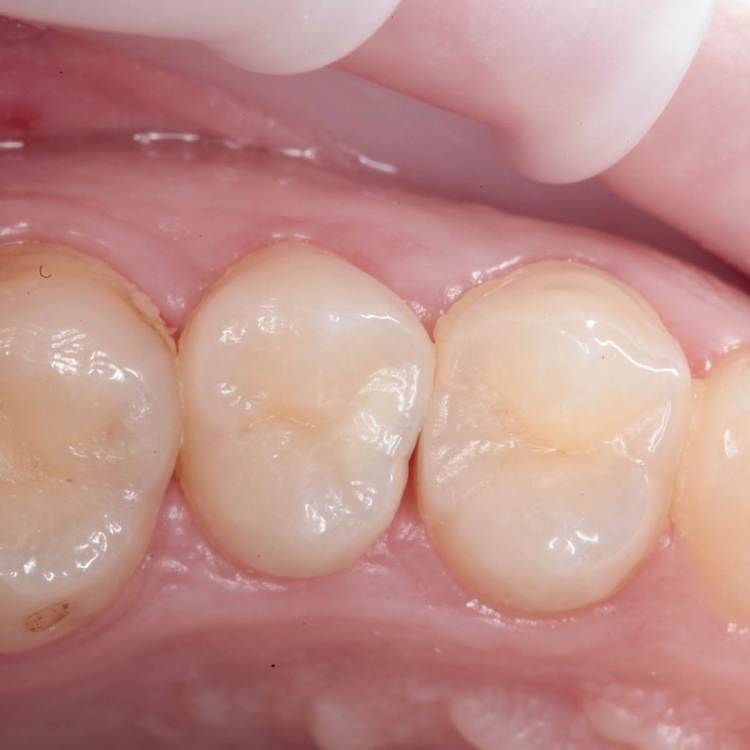

Глубина полости ниже уровня десневого края на 2-3 мм. Коагуляция, ENDO, анатомичный билдап, проверка качества реставрации и отсутсвие нависающего края (интерпроксимальный снимок), рекомендации.

На следующий день никаких жалоб.

Эндо 25.06, 40.04, 60.02. Обтурация инжекторной техникой. Восстановление гармонайз а3 и желтая текучка от эстелайта (говорят ее сняли с производства, жаль, очень классный материал был)